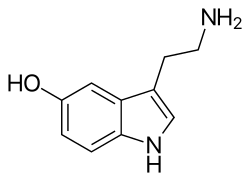

Serotonin system

The serotonin created by the brain comprises around 10% of total body serotonin. The majority (80-90%) is found in the gastrointestinal (GI) tract.[15][16] It travels around the brain along the medial forebrain bundle and acts on serotonin receptors. In the peripheral nervous system (such as in the gut wall) serotonin regulates vascular tone.

Serotonin pharmacology

- Selective serotonin reuptake inhibitors (SSRIs) such as fluoxetine are widely used antidepressants that specifically block the reuptake of serotonin with less effect on other transmitters.[17][18][19]